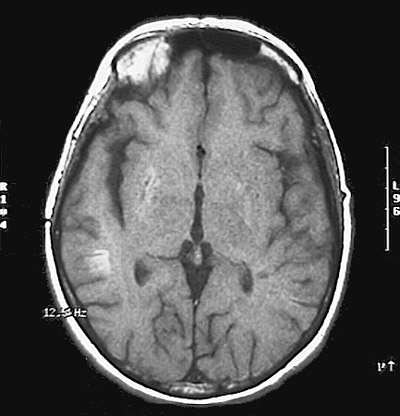

Click on the areas of infarction in the MRI scan above:

This magnetic resonance imaging scan demonstrates subacute infarctions in the

right basal ganglia

and also near the grey-white junction in the

posterior parietal region

.